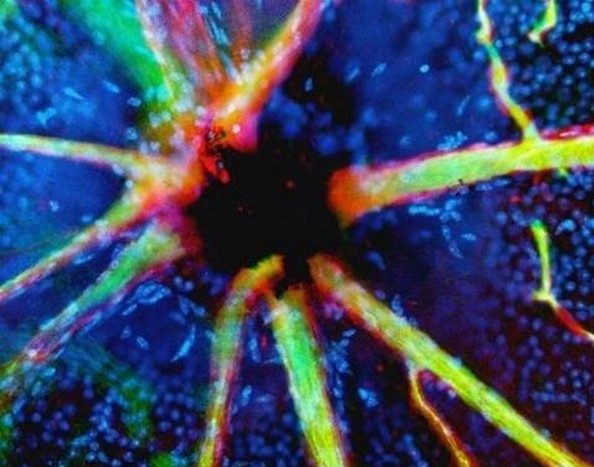

6. Очи (ретина)